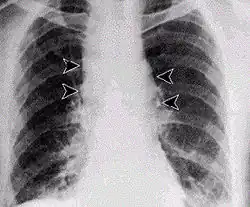

Респираторная инфекция у человека встречается относительно редко и представляет собой две стадии[8]. Она заражает лимфатические узлы сначала в грудной клетке, а не в самих лёгких, состояние, называемое геморрагическим медиастинитом, вызывая кровяное скопление жидкости в грудной полости, что вызывает одышку. Первый этап вызывает простудные и гриппоподобные симптомы. Симптомы включают в себя лихорадку, одышку, кашель, усталость и озноб. Это может длиться от нескольких часов до дней. Часто многие смертельные случаи от ингаляционной сибирской язвы происходят тогда, когда она ошибочно принята за простуду или грипп и пострадавший не ищет лечения до второй стадии, что на 90 % смертельно. Вторая (пневмония) стадия возникает, когда инфекция распространяется из лимфоузлов в лёгкие. Симптомы второй стадии развиваются внезапно после нескольких часов или дней первой стадии. Симптомы включает высокую температуру, крайнюю одышку, шок и быструю смерть в течение 48 часов при смертельных случаях. Уровень смертности в прошлом составлял более 85 %, однако при раннем лечении (наблюдавшемся при заболеваниях сибирской язвой в 2001 году) наблюдаемый уровень смертности снизился до 45 %[7]. Различие между лёгочной сибирской язвой и более распространёнными причинами респираторных заболеваний имеет важное значение для того, чтобы избежать задержек в диагностике и тем самым улучшить результаты. Для этого разработан алгоритм[9].